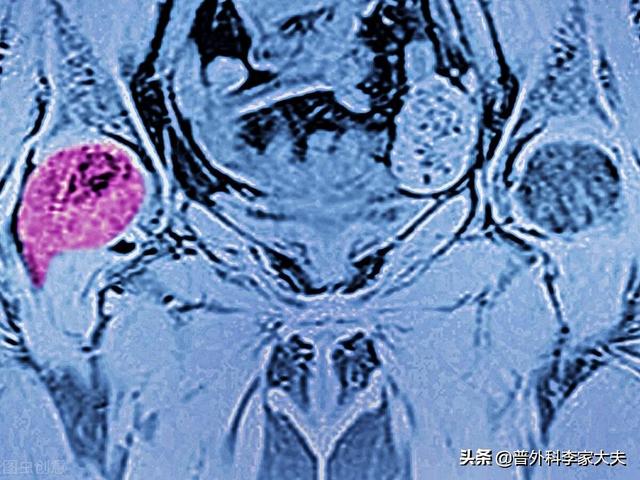

この患者だ。左股関節痛、大腿骨頭壊死を心配したが、肺がん骨転移と判明。

骨転移の部位は通常、原発性癌病巣と関連しており、一般的に腫瘍からの距離が近いほど転移の確率は高くなる。乳癌は胸部にあるため、胸骨と肋骨の骨転移が最も多く、次いで脊椎の胸椎と腰椎、肺癌の骨転移では脊椎と四肢、腎臓癌と頸癌の転移では腰椎と骨盤の転移が最も多く、前立腺癌の転移では脊椎全体と四肢が転移部位となる。

背骨は血流が豊富なため、ほとんどのがん転移の第一選択となる。 背中やその他の部位に持続的な「蟻地獄のような」痛みがあり、がんの既往歴や家族歴がある場合は、警戒が必要である。